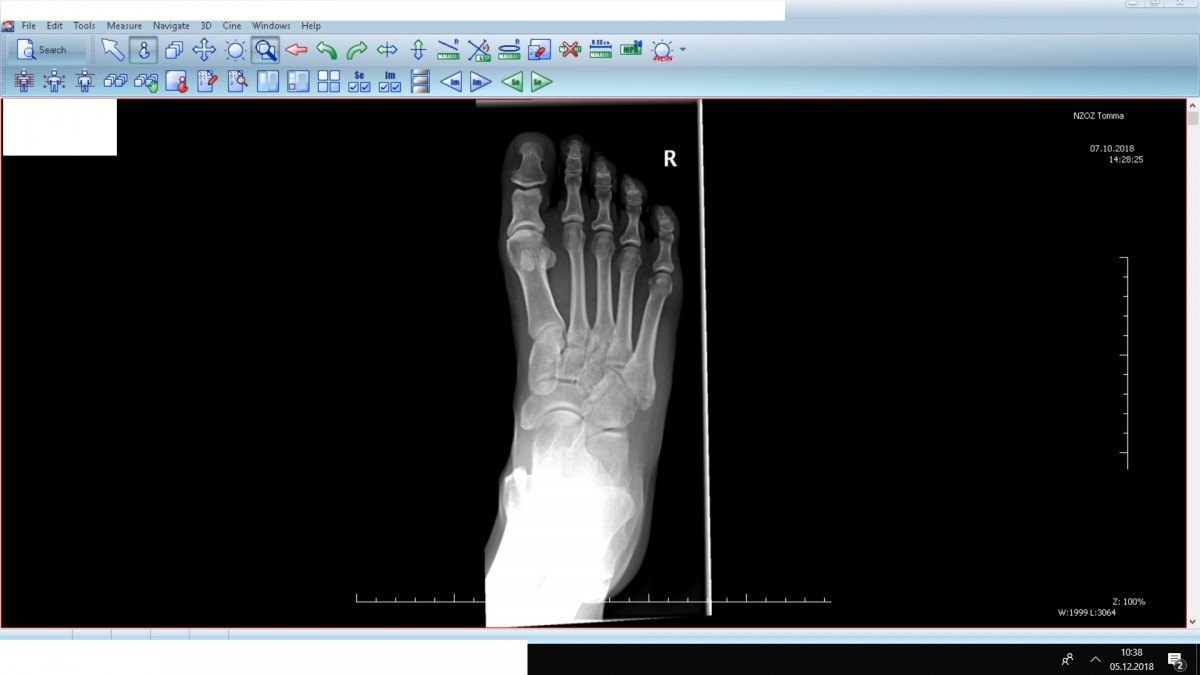

Witam 2 dni temu złamałem 5tą kość śródstopia. W opisie rtg informacja złamanie bliższej części trzonu V kości śródstopia P. W strukturach kostnych stawu skokowego P i stopy P zmian pourazowych nie widać. Mam pytanie ile czasu potrzeba aby dojść... Witam 2 dni temu złamałem 5tą kość śródstopia. W opisie rtg informacja złamanie bliższej części trzonu V kości śródstopia P. W strukturach kostnych stawu skokowego P i stopy P zmian pourazowych nie widać. Mam pytanie ile czasu potrzeba aby dojść do siebie? I jak np spac z tą nogą czy ma być uniesiona? Czy ruszać od czasu do czasu palcami w tej nodze?